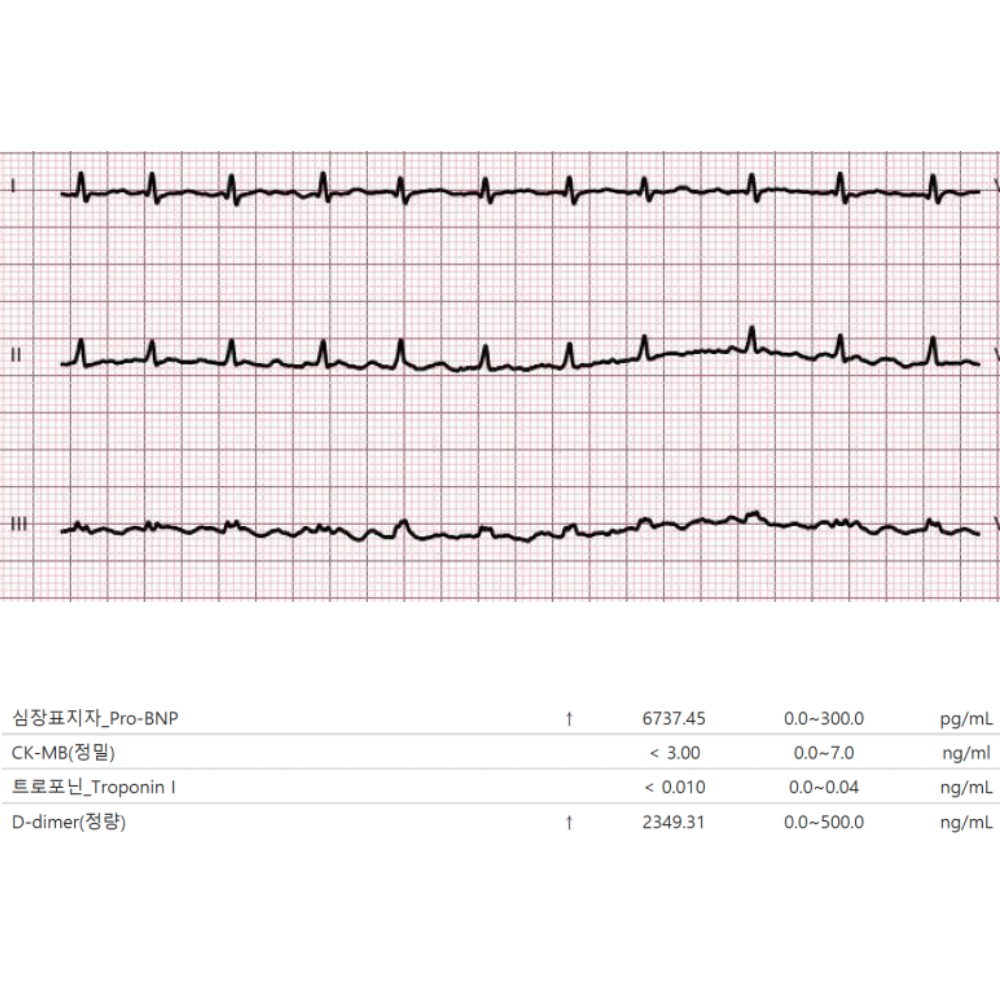

심장 기능 혈액검사

심근 손상과 심부전 평가를 위한 혈액검사로, 급성관상동맥증후군 감별과 예후 평가에 유용합니다.